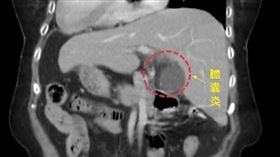

8旬嬤腹痛就醫 發現竟是「鏡面人」

新竹一名80多歲阿嬤日前左上腹痛就醫,照臨床經驗判斷...